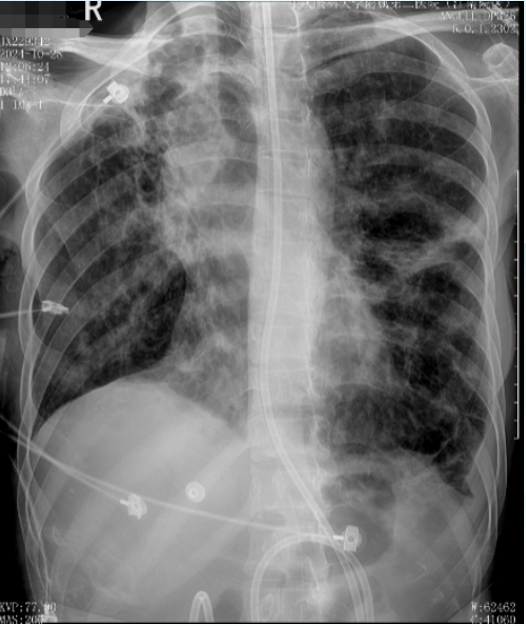

入院胸部CT:双肺多发支气管囊、柱状扩张,管壁增厚,部分管腔内见密度增高影充填,周围多发斑片状、结节状密度增高影,左肺上叶部分肺实变,边缘模糊,右肺中上叶肺体积缩小;双肺门及纵隔多发增大淋巴结;双侧胸膜增厚,左侧胸腔少量积液;心包少量积液。肺动脉稍增宽(图1)。考虑为双肺多发支气管扩张伴黏液栓及周围感染,其中左肺上叶部分肺实变,右肺中上叶慢性肺不张;双肺门及纵隔多发增大淋巴结;双侧胸膜增厚;左侧胸腔少量积液;心包少量积液;肺动脉高压改变。

图片

1  患者入院胸部CT(2024-09-20)